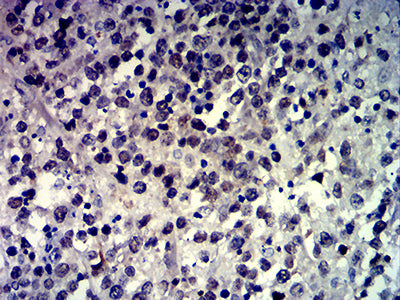

Immunohistochemical analysis of paraffin-embedded human colon tissues using MSH6 mouse mAb with DAB staining.

Immunohistochemical analysis of paraffin-embedded human brain tumor tissues using MSH6 mouse mAb with DAB staining.